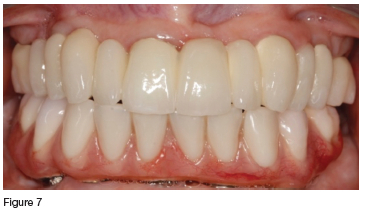

In consultation with the patient, it was decided that, although compromised, the clinician would try to save all the maxillary teeth. Initial treatment included endodontic therapy to address the pulpitis and pain in the fractured 13, followed by crown preparations on all of the remaining maxillary teeth. These were then used as abutments for the definitive prosthesis, which was a telescopic crown-retained porcelain fused to metal fixed partial denture (figures 4, 5 & 6). The mandible was restored with an acrylic veneered implant supported hybrid prosthesis (figure 7).

In the maxilla, the porcelain prosthesis remained intact with no fractures for 13 years (figures 8 & 9), however there was a single event of cement failure (figure 10) at year 12 in 2022. This event was easily managed through sandblasting the intaglio surface of the FPD and re-cementing it. The mandibular acrylic prosthesis also remained intact and functional for over 13 years, but did exhibit ±2.5 mm occlusal wear during this time. Additionally at year seven (2019) and year ten (2022) it had two separate events requiring replacement of the screw access hole closure material which had been lost (figures 9 & 11). No implant or framework complications were observed, nor was there any noticeable bone loss in either the maxilla or mandible (figure 8). The patient reported high satisfaction with both her aesthetics and chewing efficiency.